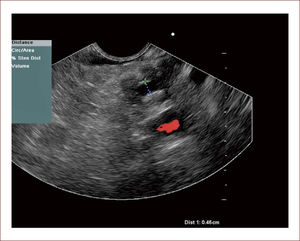

En este sentido nosotros, iniciamos un proyecto de preparación en citología elemental, pudiendo en la actualidad realizar punciones, sacar muestra y citología y una de las placas colorearla con Hematoxilina Eosina. En ese mismo momento se lee en sala, la lectura solo dice: Hay o no muestra. Mientras tanto el paciente está sedado y si hay muestra se acaba el procedimiento, si no la hay, se punciona de nuevo hasta lograr el objetivo. Esto mejora la confiabilidad del examen, disminuye futuros exámenes. Con esto, hemos logrado aumentar la sensibilidad de nuestras muestras de un 60% antes de realizado, a un 90%. De todos los pacientes tenemos placas de archivo y hacemos seguimiento con patologías. Figura 9.